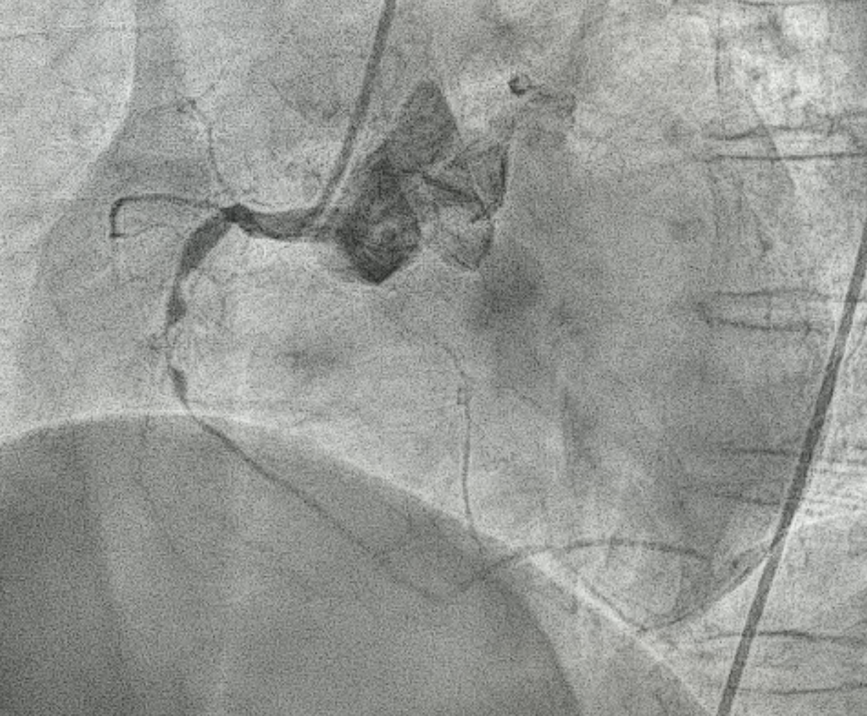

After explaining to the patient, she refused CABG and decided for PCI. 6F SAL1 as guiding catheter, starting intervention from RCA. Pressure damping was noted after engagement. While wiring Fielder FC to RCA, extravasation occurred followed by hypotension, bradycardia and nausea.IV saline challenge, inotropics agent were prescribed to stablelize the patient. Echogram showed no tamponade.

The SAL1 guiding catheter was unstable, jumping in and out the ostium. We deployed PK Papyrus 2.5 x 20 mm stent graft to dRCA quickly and planned to deployed another DES to p-dRCA. However, the patient agitated and the whole system was removed, leaving severe spiral dissection, starting from the ostium to middle RCA.We tried to wire FC, XTA and sion balck to true lumen but fail. Switched to 6F JR guiding but still fail.We wired FC to distal RCA with parallel wire technique and checked IVUS. The distal wire was over true lumen, but false lumen wiring was noted since proximal RCA.We wired XTA to true lumen under IVUS image. Then true lumen wiring was completed.We dilated with 1.5 balloon. Followed by Ryurei 2.50 x 15 mm to mRCA.We deployed Ultimaster Tansei 3.00 x 38 mm and Ultimaster Tansei 4.00 x 18 mm to p-dRCA.Post-dilated with 3.0, 3.5, and 4.0 NC balloon to RCA.The final IVUS showed well stent expansion.The final flow is good. We closed the procedure smoothly.